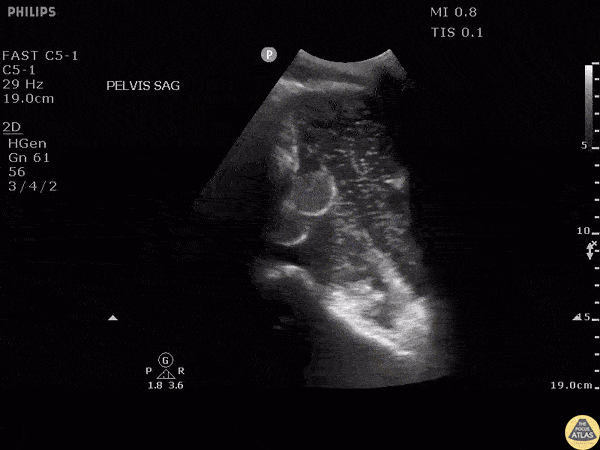

POCUS reveals air bubbles rising in a patient with a perforated bowel obstruction resulting in a pneumoperitoneum.